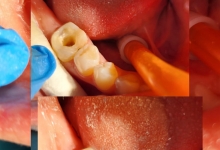

TRATAMENTUL DE CANAL

DEVITALIZARE

PREPARARE 1 CANAL RADICULAR

PREPARARE 2 CANALE RADICULARE

PREPARARE 3 CANALE RADICULARE

IRIGAREA CANALELOR RADICULARE

TRATAMENT INTERIMAR PENTRU GANGRENA SAU ALTE PATOLOGII

OBTURATIA DE CANAL

DEZOBTURARE